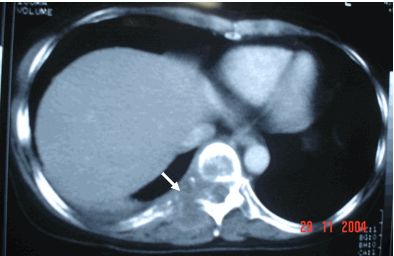

Ung thư phổi thứ phát kiểu thả bóng trên phim chụp phổi thẳng, CT scan

Trên đây là một số thông tin và hình ảnh về bệnh ung thư phổi thứ phát kiểu thả bóng trên phim chụp phổi thẳng, CT scan, hy vọng sẽ giúp các bạn có được những hiểu biết về bệnh để có hướng điều trị phù hợp và hiệu quả!